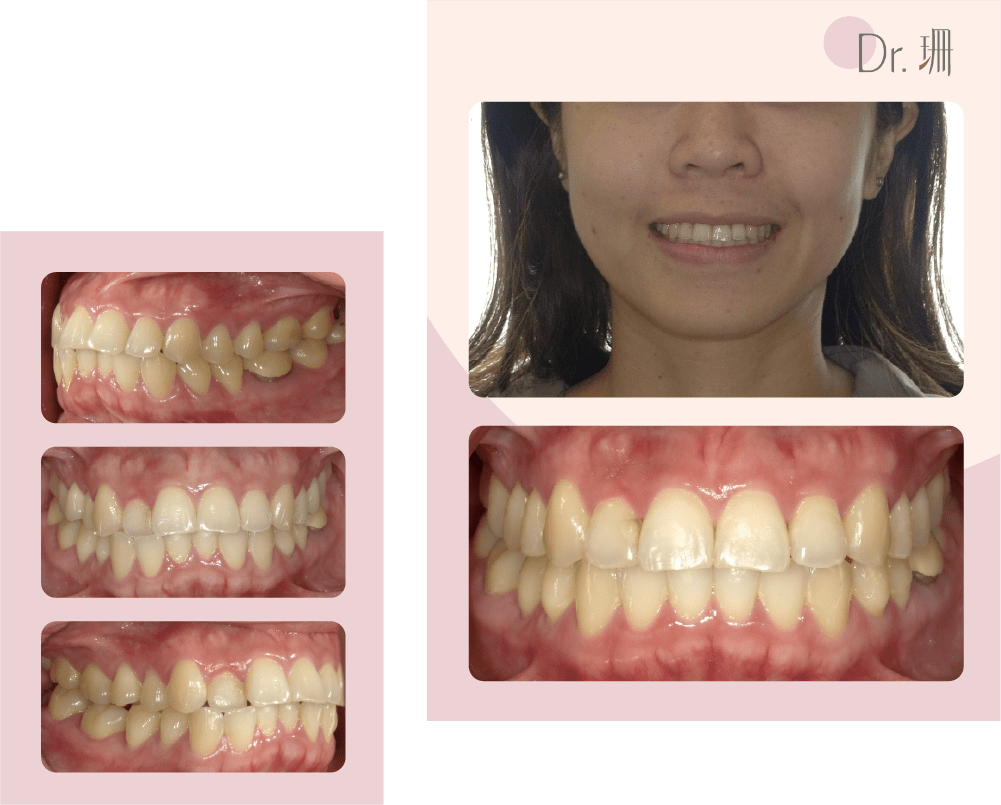

隱適美矯正牙齒過程

牙齒矯正前後外觀及牙齒變化

阿琪療程結束時真的很讓我驚艷感動! 因為輪廓明顯改善,看上去年輕許多,衣服也越穿越帥,整個氣息都不一樣了呢!